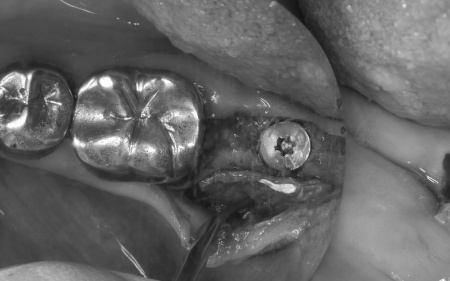

まずは左下奥歯に装着されていた被せ物を慎重に除去し、歯根の状態を直接確認します。

その結果、歯根破折が明確に認められたため、歯の温存は困難であると判断しました。

歯根破折が疑われました。